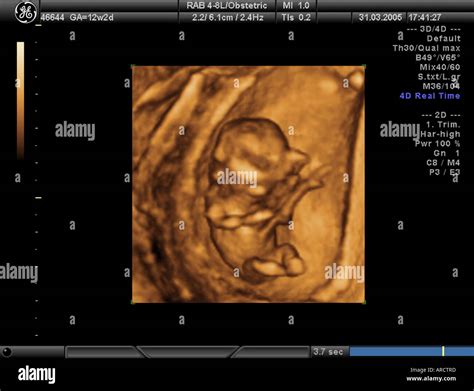

A 9 weeks pregnant ultrasound is typically performed to assess the baby's growth and development. At this stage, the ultrasound can provide detailed images of the fetus, allowing healthcare providers to measure the baby's size, check for a heartbeat, and evaluate the overall health of the pregnancy. This scan is usually done transabdominally, meaning the ultrasound probe is moved over your belly, or transvaginally, where the probe is inserted into the vagina for a clearer view.

• Size: Your baby is about the size of a grape, measuring approximately 0.63 inches (1.6 centimeters) in length and weighing around 0.07 ounces (2 grams).

• Heartbeat: The baby's heartbeat is usually detectable by ultrasound, and it may be visible as a rapid fluttering.

• Organs and Systems: Major organs and systems, such as the brain, heart, and lungs, are beginning to form. The tail, which is a normal part of early development, is also visible.

• Limbs: The baby's arms and legs are becoming more defined, with small buds that will eventually develop into hands and feet.

• Facial Features: The eyes and ears are starting to take shape, and the mouth and tongue are forming.

• Normal Development: Ensuring that the baby's organs, limbs, and facial features are developing as expected.

• Heartbeat: Confirming a strong and regular heartbeat.

• Growth: Checking that the baby's size is appropriate for the gestational age.